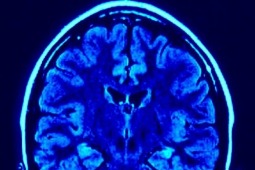

Mózg wyziębionego 2-latka działa sprawnie

Mózg 2-latka, który spędził 7 godzin na mrozie nie jest uszkodzony - dowiedział się reporter Radia ZET. Dziecko ratują lekarze Uniwersyteckiego Dziecięcego Szpitala Klinicznego w Prokocimiu w Krakowie. Na razie nie wiadomo jaki będzie jego stan po wybudzeniu ze śpiączki farmakologicznej, co jest planowane na środę.

Specjaliści ze Szpitala Dziecięcego w Krakowie-Prokocimiu przyznają, że z takim przypadkiem głębokiej hipotermii nie miał do czynienia nikt na świecie. Uratowano dotąd osobę z temperaturą około 13 stopni Celsjusza, temperatura chłopca spadła do 12 stopni Celsjusza.

Przywracanie do życia małego Adasia, to tak naprawdę odkrywanie możliwości ludzkiego organizmu nie poznanych jeszcze przez medycynę. Gdy chłopiec trafił na oddział medycy lekarze mówili o bardzo prawdopodobnych uszkodzeniach mózgu, nie z powodu niskiej temperatury, ale długiego czasu - kiedy krążenie krwi prawie ustało, a mózg był niedotleniony.